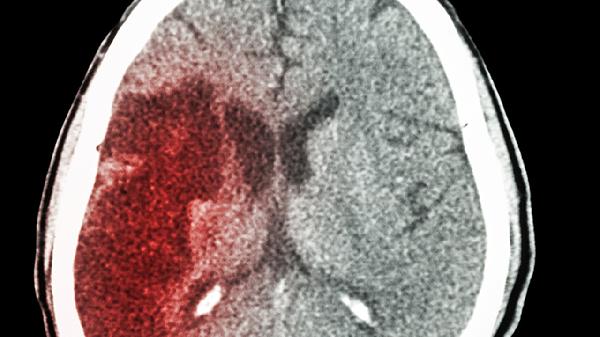

腦出血可能引起腦疝。腦疝是腦組織因壓力差發(fā)生移位并壓迫腦干等結(jié)構(gòu)的危重并發(fā)癥,腦出血后血腫占位效應(yīng)或腦水腫導(dǎo)致顱內(nèi)壓升高時(shí)可能誘發(fā)腦疝。

腦出血后血腫直接壓迫周圍腦組織,或繼發(fā)腦水腫使顱內(nèi)壓力急劇升高,可能迫使部分腦組織向壓力較低區(qū)域移位。常見如小腦幕切跡疝,表現(xiàn)為意識(shí)障礙加深、瞳孔不等大及對(duì)側(cè)肢體癱瘓;枕骨大孔疝則可能突發(fā)呼吸心跳驟停。這類情況多發(fā)生于出血量大、部位深或未及時(shí)干預(yù)的患者中。